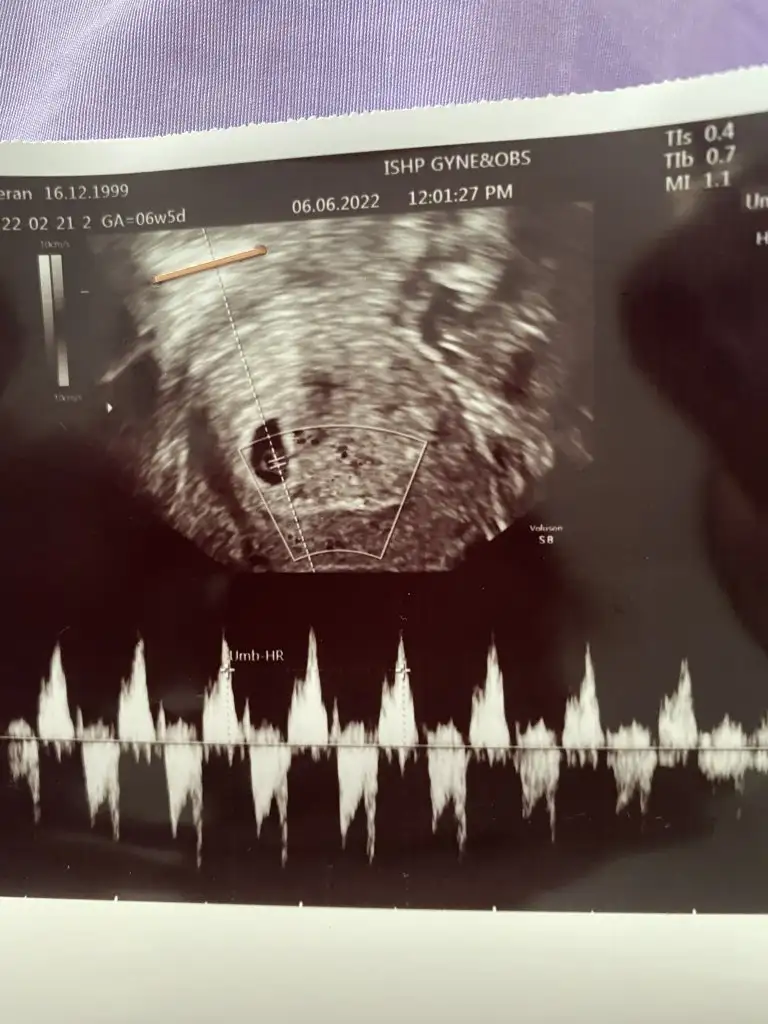

Merhaba cnm birde benimkine bakarmisin 6+3 vajinal ultrason

Eklentiler

• 81D556A9-5A95-4DF3-9A5E-DDC6CA75884E.webp

46,3 KB · Görüntüleme: 99